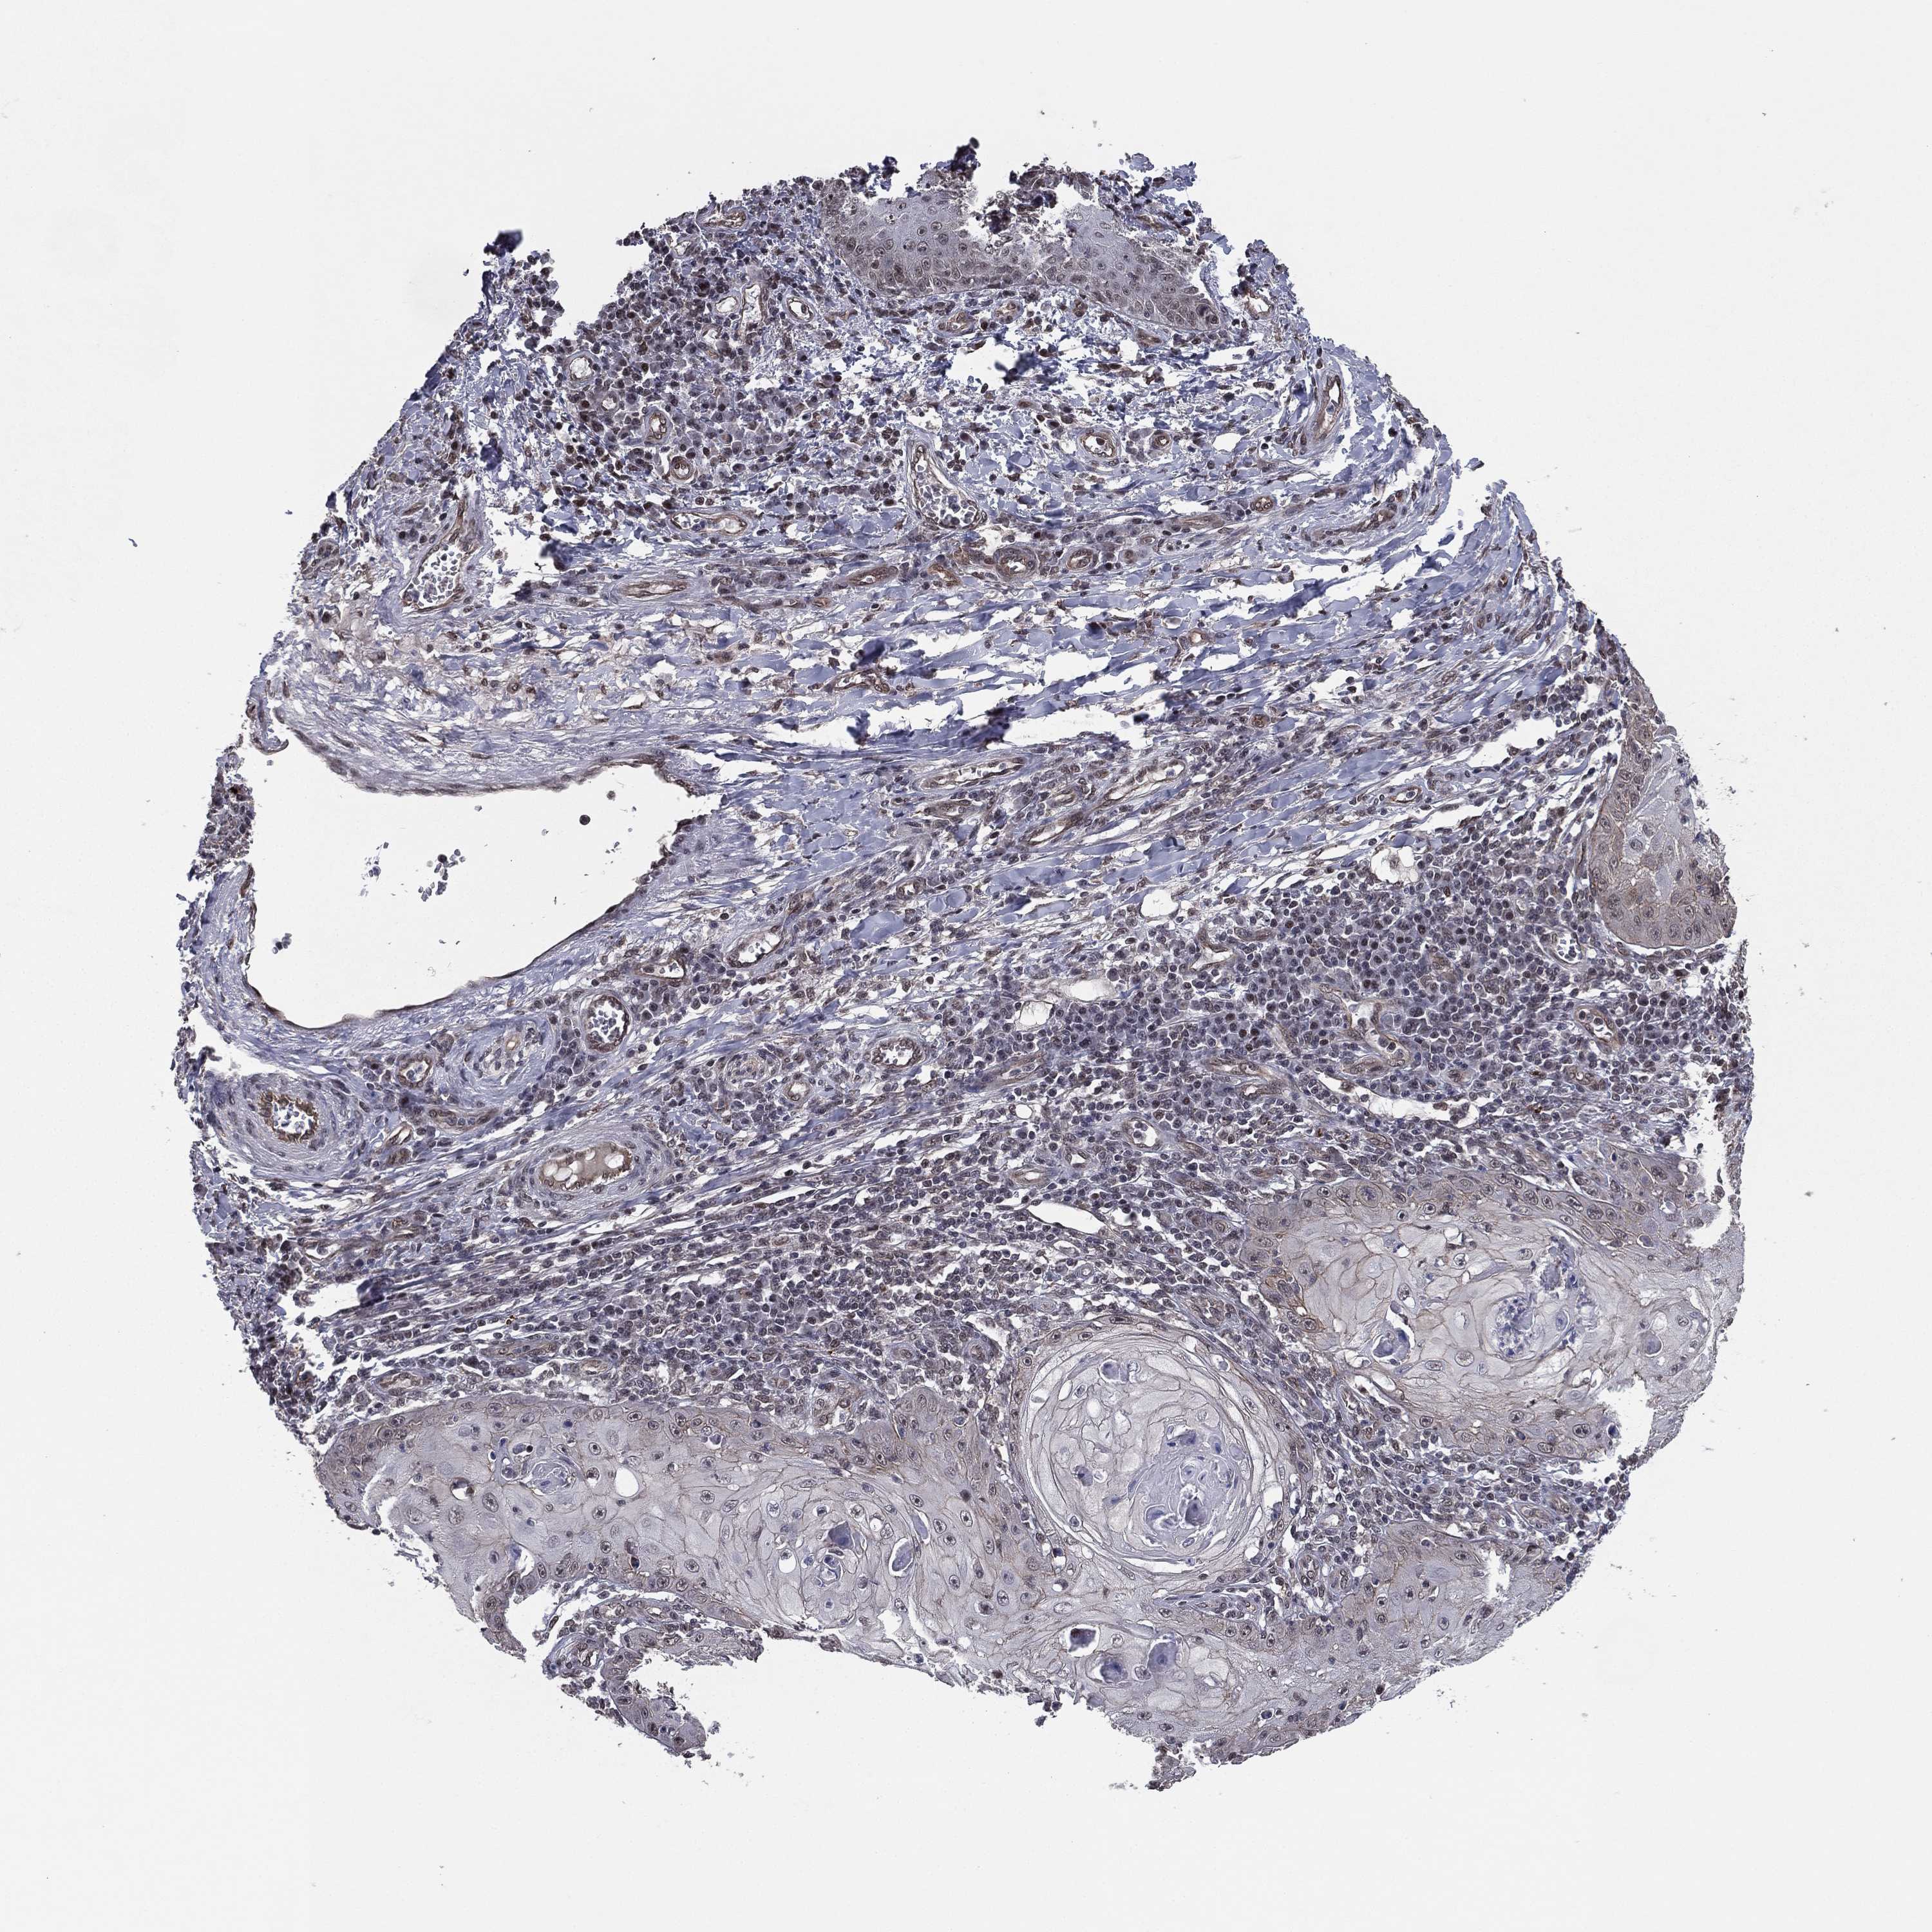

SKIN CANCER - Protein expressioni

A mouse-over function shows sample information and annotation data. Click on an image to view it in a full screen mode. Samples can be filtered based on level of antibody staining by selecting one or several of the following categories: high, medium, low and not detected. The assay and annotation is described here.

Antibody stainingi

Antibody staining in the annotated cell types in the current human tissue is reported as not detected, low, medium, or high, based on conventional immunohistochemistry profiling in selected tissues. This score is based on the combination of the staining intensity and fraction of stained cells.

Each image is clickable and will lead to virtual microscopy that enables deeper exploration of all samples and also displays staining intensity scores, fraction scores and subcellular localization as well as patient and tissue information for each sample.

Antibody HPA004174

Antibody CAB002617

Staining

High

Medium

Low

Not detected

Intensity

Strong

Moderate

Weak

Negative

Quantity

>75%

75%-25%

<25%

None

Location

Nuclear

Cytoplasmic/membranous

Cytoplasmic/membranous,nuclear

Basal cell carcinoma

Squamous cell carcinoma, NOS